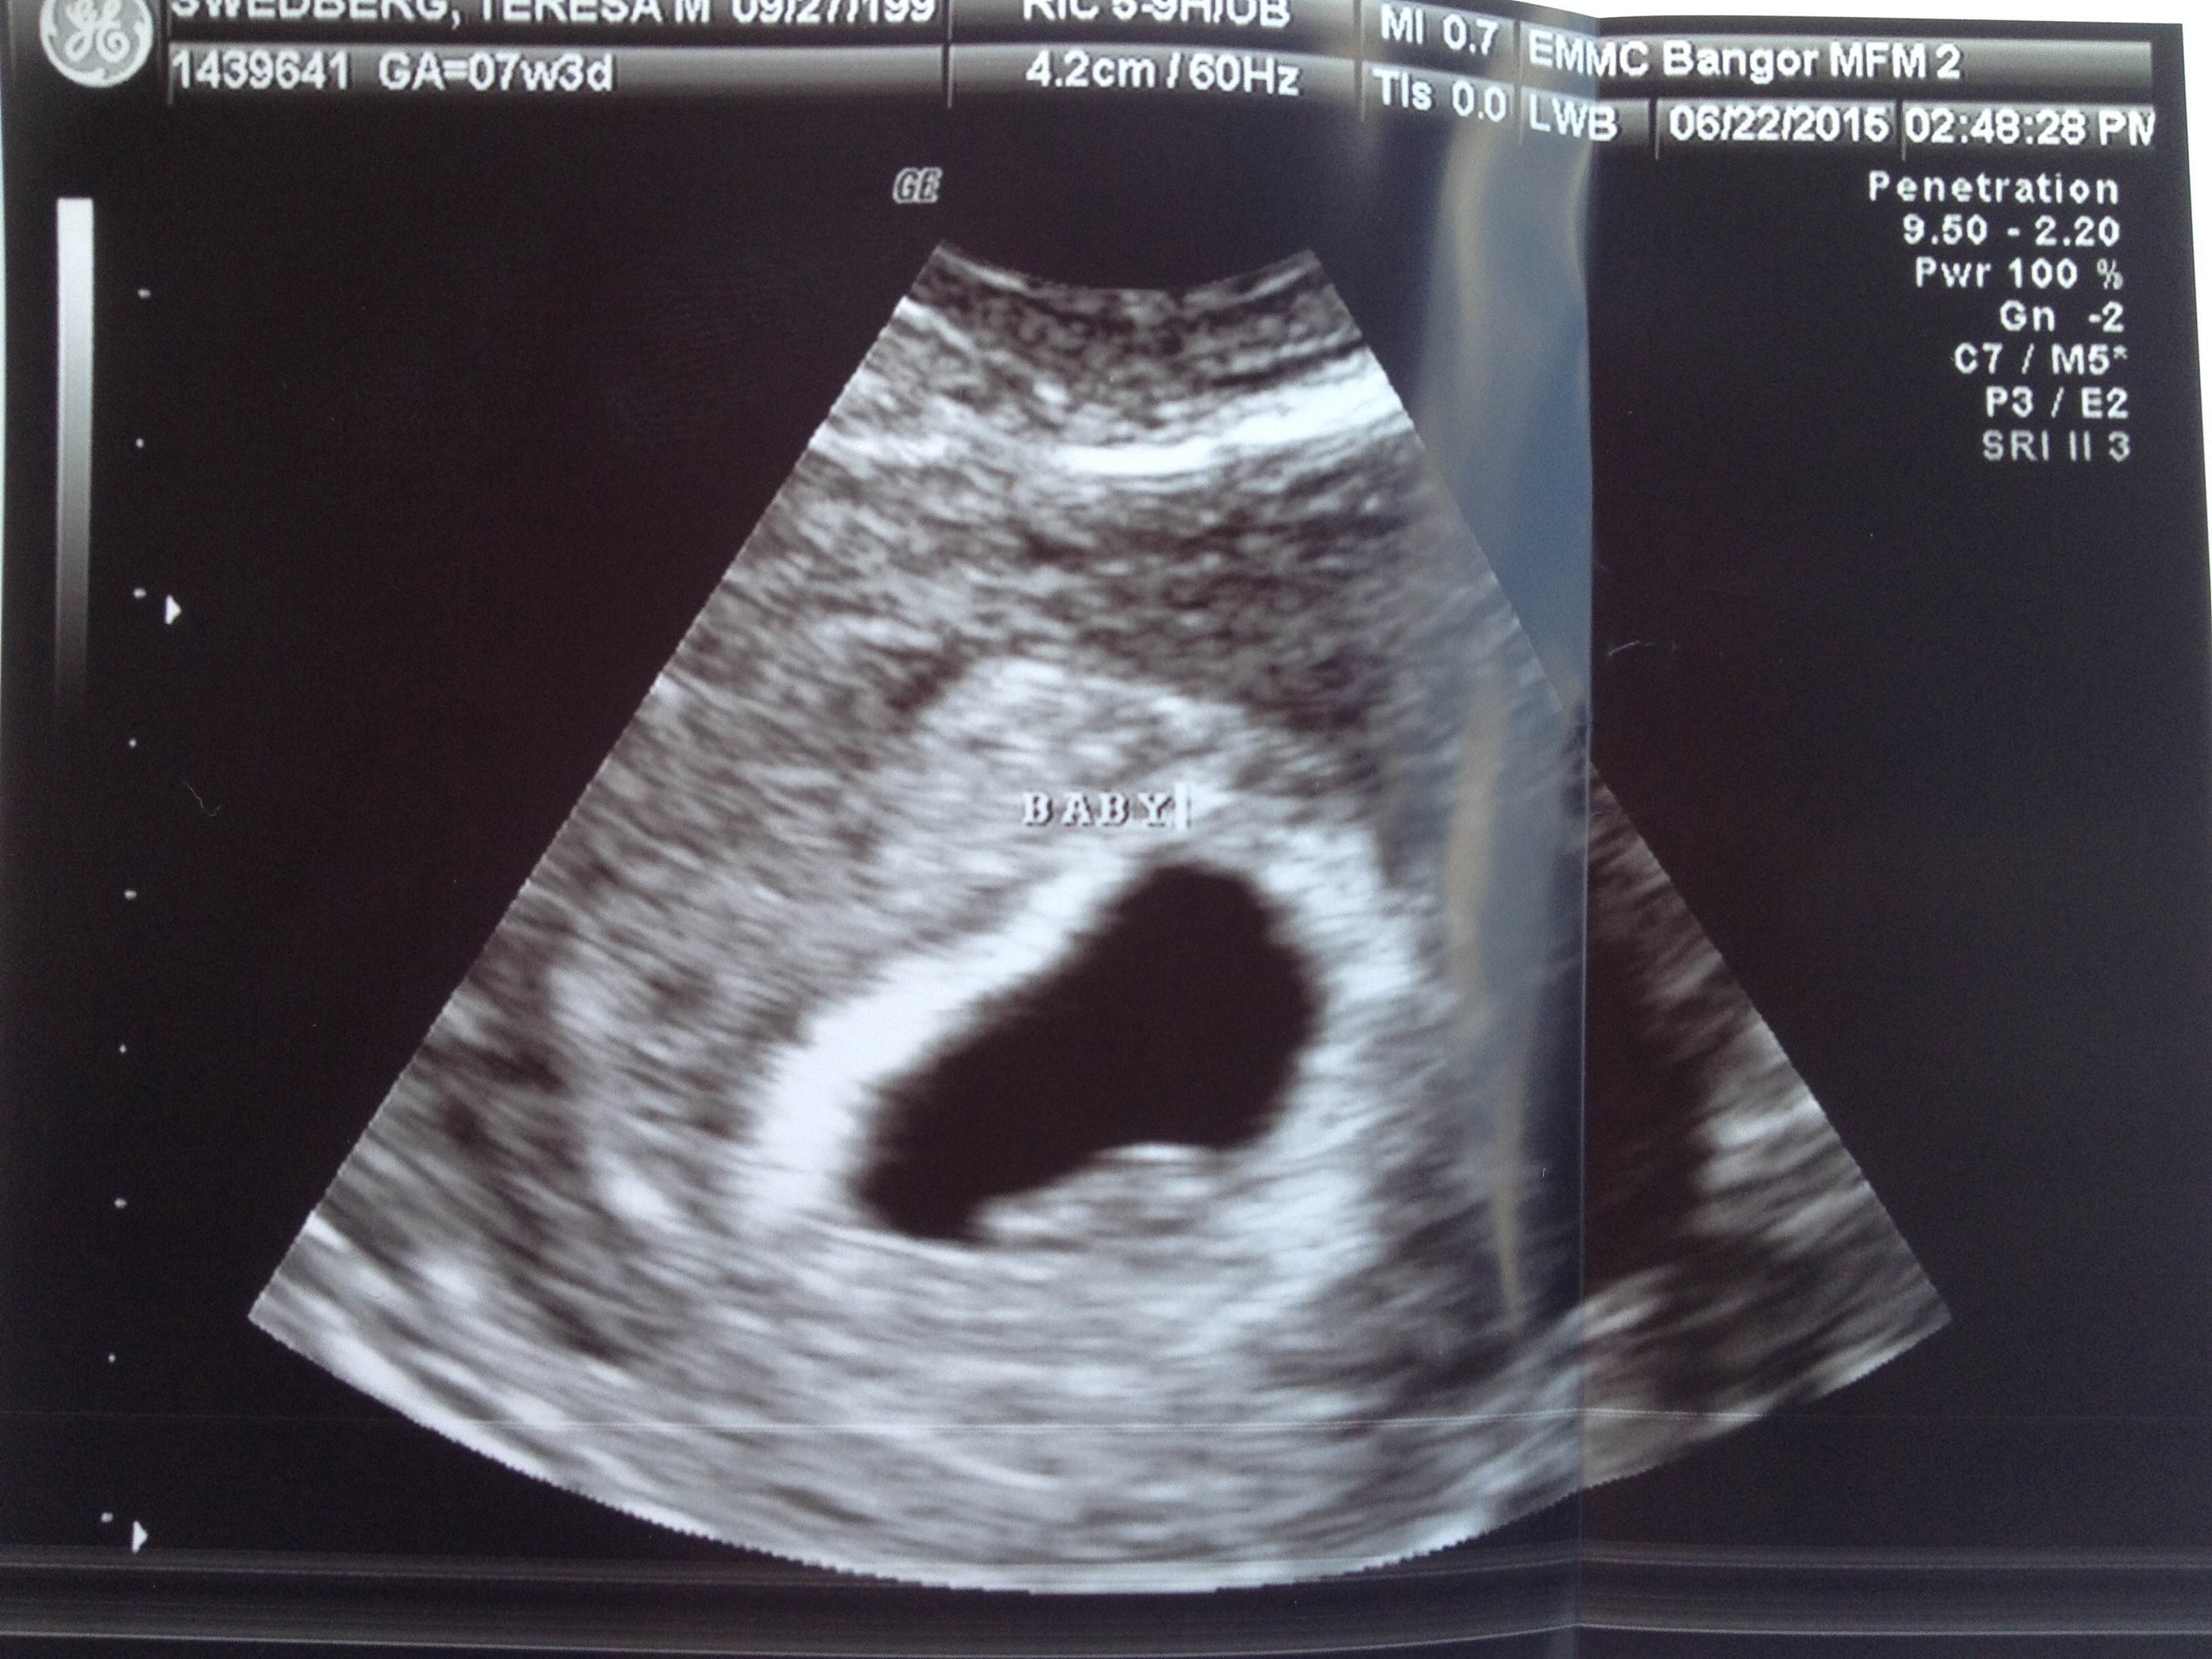

• So glad I get to finally post on this thread! First US today. I was really worries because my progesterone was low, but baby looks good :) heartbeat was 143. Not as far along as we originally thought, but not far behind. Right at 7 weeks. Due 2/23 :)